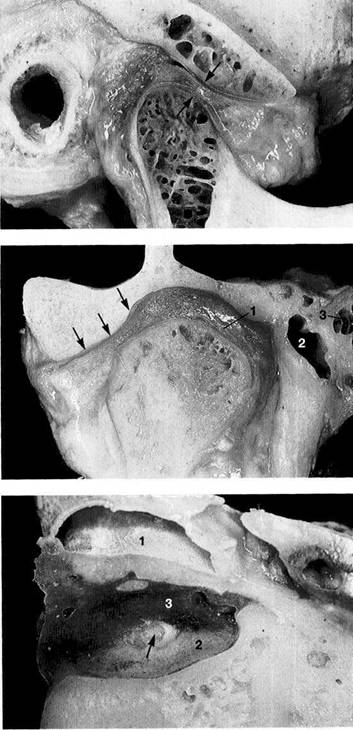

Glenoid Fossa and Articular Protuberance

The temporal portion of the joint can be divided into four functional parts from posterior to anterior: postglenoidal process, glenoid fossa, articular protuberance, and apex of the eminence. The inclination of the protuberance to the occlusal plane varies with age and function (Kazanjian 1940), but is 90% determined at the age of 10 years (Nickel et al. 1988). Three fissures can be found at the transition to the tympanic plate of the temporal bone: the squamotym-panic, petrotympanic, and petrosquamous fissures (Fig. 28). In patients with disk displacement, these fissures are fre-

quently ossified (Bumann et al. 1991). Under physiological conditions the only parts of the temporal portion of the joint that are covered with secondary cartilage are the protuberance and the eminence (Fig. 31). Secondary cartilage is formed only when there is functional loading. Before the fourth postnatal year stimulation of the cells of the perio-seum leads to the formation of secondary cartilage (Hall 1979, Thorogood 1979, Nickel et al. 1997). With no persisting functional load the chondrocytes of the condyle would differentiate into osteoblasts (Kantomaa and Hall 1991).

Joint

region of the temporal

bone

Inferior view of the temporal portion of a defleshed temporomandibular joint. Near the upper border of the picture is the articular eminence (1) and at the far left is the external auditory meatus (2). In the posterior portion of the fossa the squamotympanic fissure (3) is found laterally, and the petrosquamous (4) and petrotympanic (5) fissures are found medially. Both the superior stratum of the bilaminar zone and the posterior portion of the joint capsule, and sometimes also the fascia of the parotid gland can insert into these fissures.

Ossification

of the fissures

and disk displacement

Inferior view of a temporal bone with partially ossified fissures. The lateral half of the squamotympanic fissure is completely ossified (arrows). The superior stratum of the bilaminar zone can now insert only into the periosteum in this region. It has been shown that these fissures are ossified in more than 95% of patients with disk displacement, whereas in joints without disk displacement normal fissure formation prevails (Bumann et al. 1991).

Inferior view of the temporal cartilaginous joint surface and capsule attachment

Caudal view of the left temporomandibular joint of a newborn. The bony portions have been separated from the periosteum up to the circular insertion of the capsule and bilaminar zone. Part of the zygomatic arch (1) can be seen near the right border of the photograph. The fibrocartilaginous articular surfaces over the articular protuberance are thickened medially and laterally (arrows). When covered with synovial fluid they allow movements with virtually no friction (Smith 1982).

Sagittal

histological section

showing buildup of the temporal

joint components

The temporal portion of the joint can be divided into four functional components: 1 postglenoidal process, 2 glenoid fossa, 3 articular protuberance, and 4 apex of the eminence. As a rule, no cartilage can be identified within the fossa. The average thickness of the fibrous cartilage over the protuberance and the eminence is between 0.07 and 0.5 mm (Hansson et al. 1977). As this photograph shows, there can be considerable variation in thickness within the same individual.

Sagittal relationships

Macroscopic anatomical preparation showing the relation of the fossa, disk, and condyle to one another in the sagittal plane. Because the shapes of fossae and condyles vary so greatly, it is not possible to determine a universally applicable measurement of the condylar position. Although the physiological (i.e. centric) condylar position is defined as the most anterosuperior position with no lateral displacement (arrows), this position depends upon the basic neuromuscular tonus.

Frontal relationships

Macroscopic anatomical preparation showing the relation of the fossa, disk, and condyle to one another in the frontal plane. In this plane, too, there is no standard geometric arrangement of condyle and fossa because of the variability of the hard and soft tissues (Yung et al. 1990). In this preparation the disk (arrows) is displaced laterally. Structures of the bilaminar zone (1) can be identified in the medial portion of the joint. The close proximity of the joint to the middle (2) and inner ear (3) can also be observed.

Horizontal relationships

A right temporomandibular joint viewed from above showing the relation of the fossa, disk, and condyle to one another in the horizontal plane. The lateral portion of the joint is near the left border of the picture. Near the upper border a section through the external auditory meatus can be seen (1). The roof of the fossa has been removed. Near the center of the picture lies the transition from the pars posterior (2) to the bilaminar zone (3). The central perforation was created during sectioning, and through it can be seen the upper surface of the condyle (arrow).